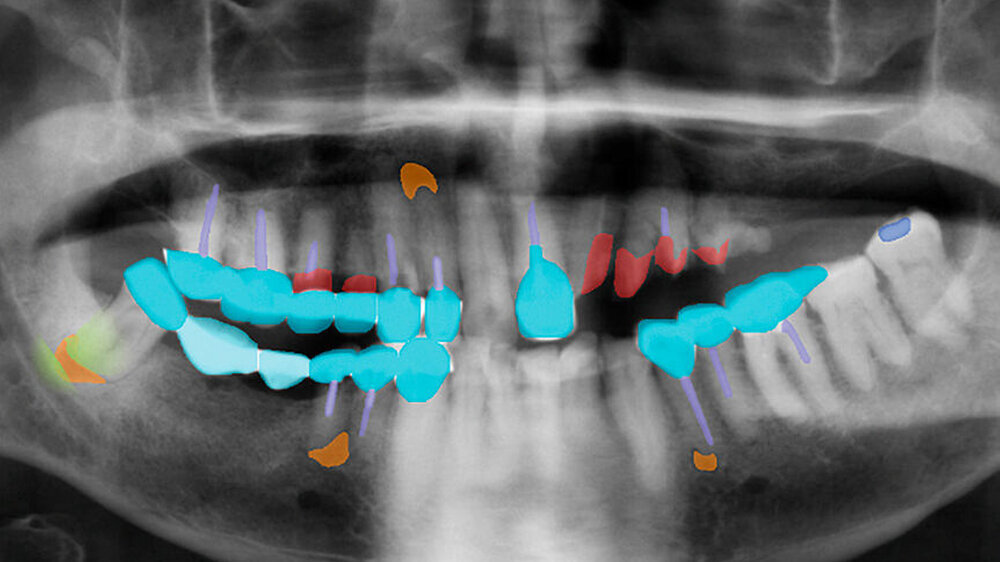

Forscher behelfen sich daher mit der Eingrenzung der relevanten Areale auf einem Bild: So kann Karies beispielsweise nur im Bereich der Zahnhartgewebe vorkommen, die meisten Zahnröntgenbilder weisen jedoch auch umfänglich andere Strukturen wie Knochen auf. Diese Areale auszublenden und dem KI-Modell nur den relevanten Bereich anzubieten, kann die Genauigkeit erheblich steigern.